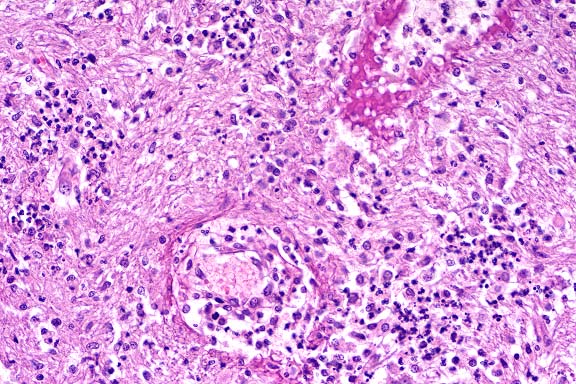

Case 1-4. Cerebrum. Demonstrates a necrotizing vasculitis of two vessels with a multifocal suppurative encephalitis. The upper vessel has a fibrinoid degeneration of its wall. 20x obj.

AFIP Diagnosis: Cerebrum, level of hippocampus: Choriomeningoencephalitis, acute to subacute, multifocal, mild to moderate, with vasculitis, Chow Chow, canine.

Conference Note: Due to section variability, not all slides have examples of fibrinoid change in vessels. When present, vascular walls of small vessels are hyalinized with loss of the endothelium. Most sections demonstrate some necrosis of vessels.